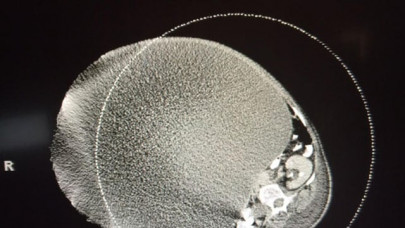

Doctors remove woman's 140-pound tumour

Patient believed her snacking habit was the cause of her being overweight